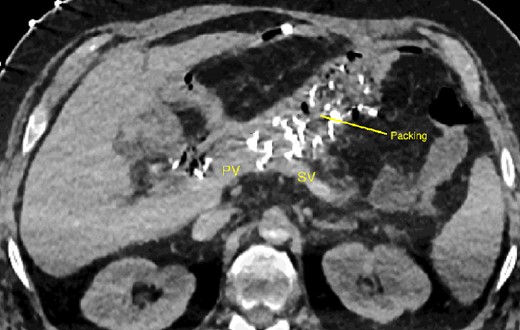

The abdominal exploration was difficult due to significant inflammatory adhesions, which can be attributed to the presence of a pancreatic fistula and the delay of relaparotomy. There was no bleeding observed within the abdominal cavity, and no bleeding was seen from the multitubular drain during the exploration. We hypothesized that the bleeding was of venous origin caused by drain-induced recurrent erosion of peripancreatic vessels, resulting in intermittent bleeding, and that removing drains could help in attaining venous hemostasis. As a result, it was decided to remove the drains. However, this resulted in a significant hemorrhage via the drain orifice. Due to failure to identify the exact origin of bleeding and without the possibility of completion pancreatectomy, we performed a damage control procedure by packing through the drain orifice. This successfully stopped the bleeding. A postoperative CT scan located the packing sponges anterior to the spleno-mesenteric confluence (SMC) (Fig. 2). A percutaneous transhepatic portography showed an irregular aspect of the SMC, without thrombi or contrast extravasation (Fig. 3). After consulting with the interventional radiology team, we placed a cover stent (Fluency™ Bard, Murray Hill, USA) in the SMC (Fig. 4). Two days later, we removed the packs, and a massive hemorrhage recurred, necessitating a new packing. The stent was not seen on a subsequent CT scan. We then performed an endovascular procedure to exclude the segment of the irregular SMC. An Amplatzer™ vascular plug (Abbott Vascular, Santa Clara, USA) was placed in the splenic vein, extending distally to just surpass the inferior mesenteric vein (IMV) insertion (Fig. 5). A cover stent was subsequently deployed in the portal vein, extending distally to the superior mesenteric vein. This allowed for the exclusion of the splenic vein segment that lies between the inferior mesenteric vein insertion point and the spleno-mesenteric confluence (Fig. 5). The packing sponges were removed 10 days later without bleeding recurrence, and the patient finally showed clinical improvement. After 3 years, the stent was visible and permeable on a follow-up CT scan. The scan showed development of venous collaterals, which drain the distal splenic vein and inferior mesenteric vein through the lesser omentum (Fig. 6).

CT scan after relaparotomy located the packs used for hemorrhage control anterior to the confluence of the portal vein and splenic vein. PV portal vein, SV splenic vein.